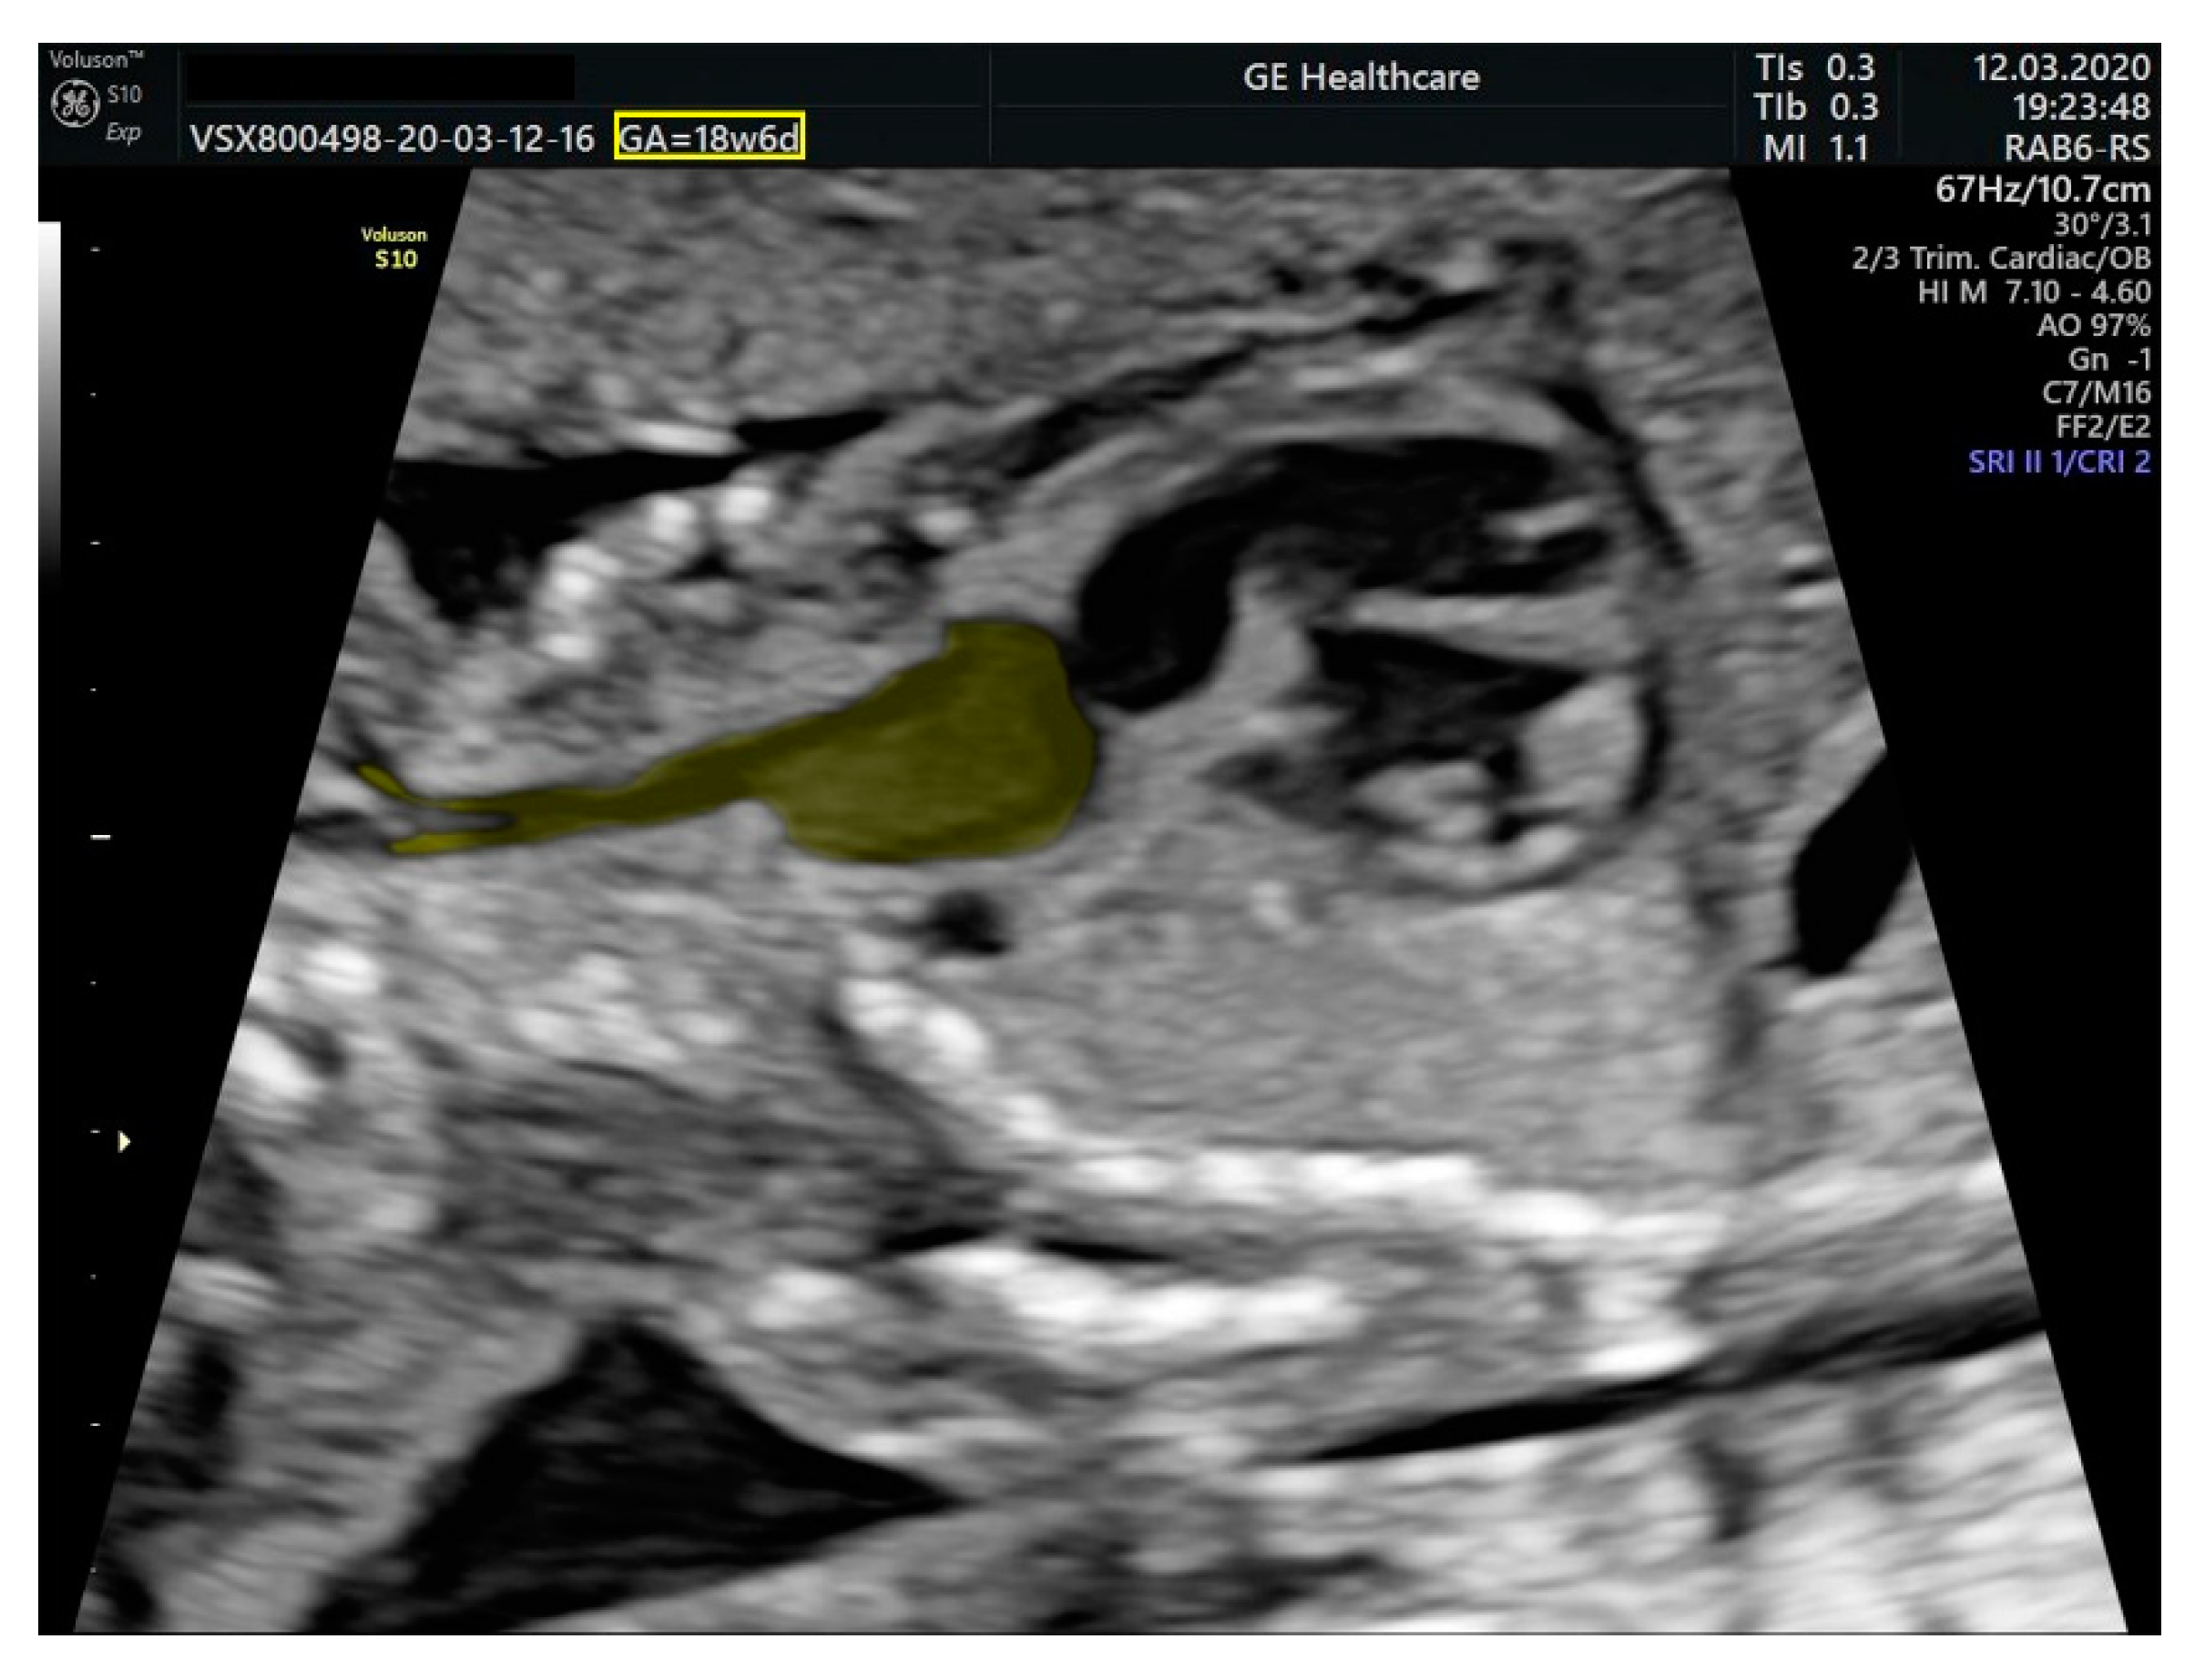

2.1. Ultrasound Findings

- an isolated aortic arch anomaly (supposedly aneurysmal dilation from which the left common carotid artery emerges) and coarctation of the aorta with the anterograde flow;

- ventricular septal defect, coarctation of the aorta, and a vascular formation located superior from the aortic arch with the appearance of an arteriovenous fistula;

- aneurysmal dilation located above the pulmonary trunk bifurcation and a dilated left common carotid artery with a retrograde flow;

- minor ventricular septal defect with a normal ductus venosus triphasic flow.